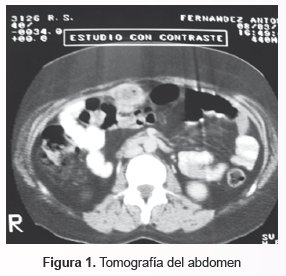

TAC de abdomen: Masa heterogénea que podría corresponder a proceso expansivo de duodeno, no obstructivo, con compromiso de cabeza de páncreas y fosa vesicular, no descartándose mets. A nivel de segmento 1 y 2 hepático. Uraco permeable (Fig. 1).